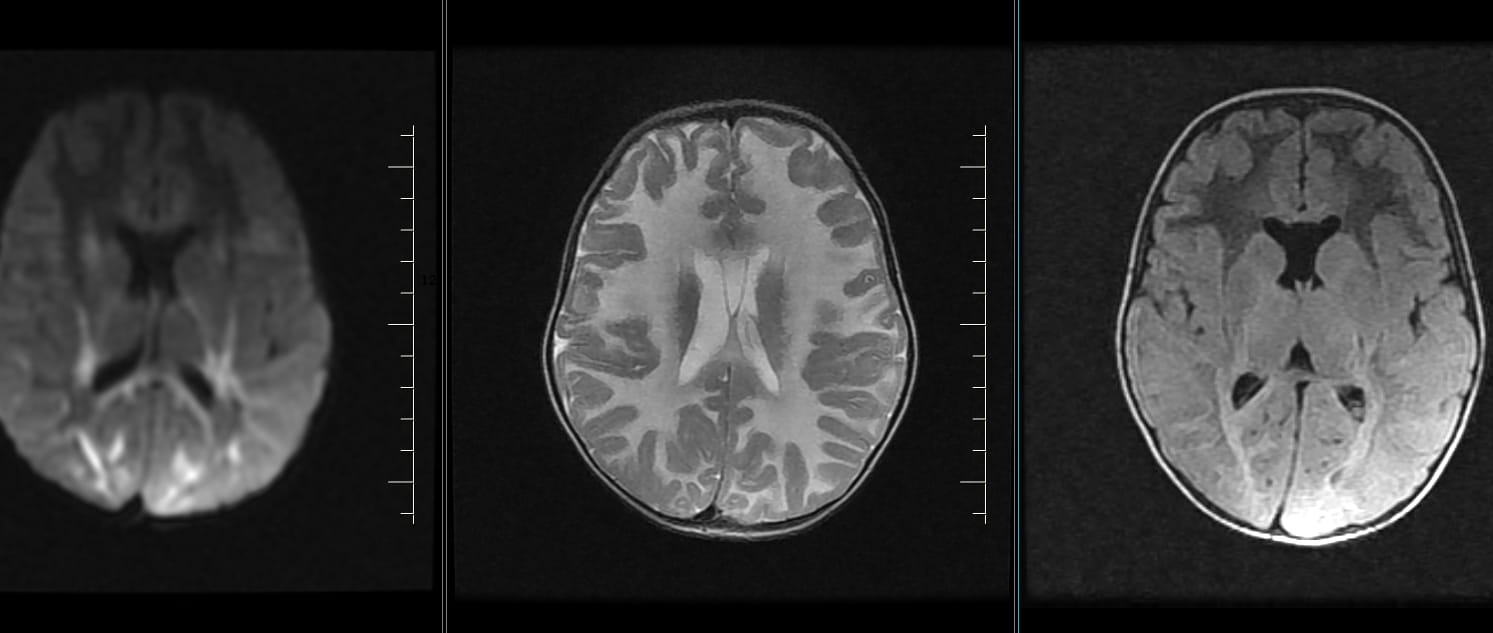

lissencephaly-pachygyria spectrum (type I)

Marked thickening and broadening of bilateral fronto-temporo-parietal, occipital gyri with gross simplification, poor formation of...